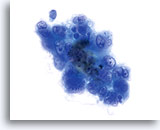

Celkernmembranen zijn verdikt en onregelmatigheden in celkernmembranen zijn golvend, in tegenstelling tot de “rattenbeet”-membranen die ook wel in squameuze laesies gezien wordt.

40x